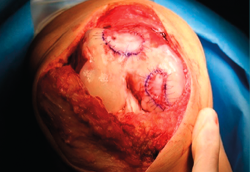

First surgery involves arthroscopy of the damaged joint. It assesses the chondral lesion to be treated and confirms whether it is amenable to the chondrocyte implantation technique (Figures 1 and 2). Other procedures are also carried out if needed, such as for example reconstruction of the anterior cruciate ligament, partial meniscectomies, meniscus implantation, patellar realignments, osteotomies, etc. Lastly, the cartilage sample is taken from a non-weight bearing zone (intercondylar zone or internal femoral condyle at its upper margin). The sample is extracted with biopsy forceps or, alternatively, using discectomy forceps. Between 3-4 rice grain-sized fragments of healthy cartilage are harvested (Figure 3). The biopsy material is placed in a sterile receptacle containing a culture medium (DMEN) (Figure 4). The material is kept at room temperature and is shipped to the laboratory as quickly as possible. A form should be completed (Figure 5), stating the joint, the location of the lesion and the size of the defect. Once in the laboratory, the sample is processed and cultured. After 4-6 weeks (depending on the case), the culture is ready for implantation.

Figure 1. Arthroscopic view of an Outerbridge grade IV acute chondral lesion of the internal femoral condyle.

Figure 2. Arthroscopic view of an Outerbridge grade IV chronic chondral lesion of the internal femoral condyle.